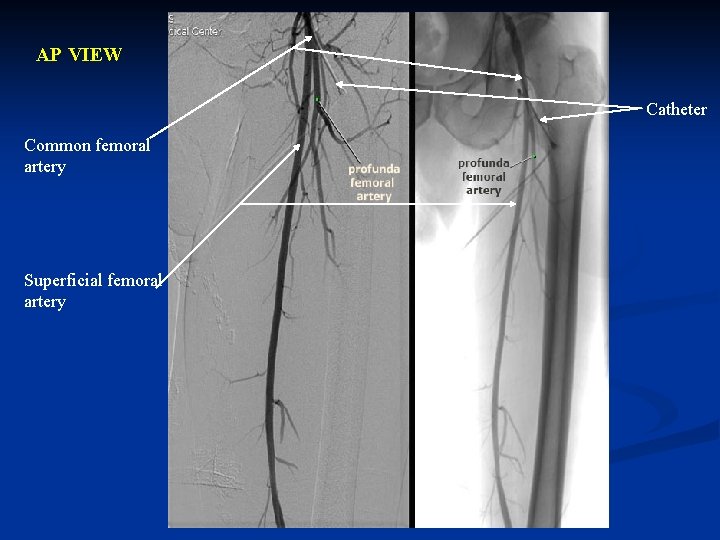

AP VIEW Catheter Common femoral artery Superficial femoral artery